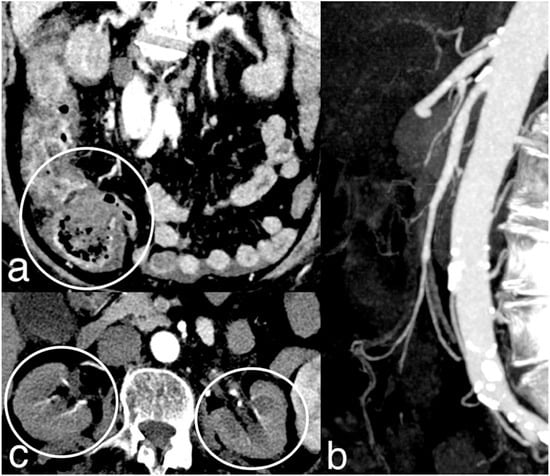

Figure 6.

NOMI. Diffuse stratified wall thickening of right colon ((a) circle) with patent mesenteric arteries (b). The 78-year-old patient had a severe systemic hypoperfusion and multi-organ failure, with bilateral kidney cortical necrosis ((c) circles) and ARDS. The patient died a few hours later.